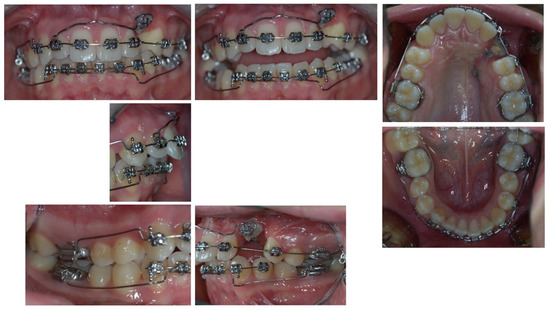

4. Follow-Up and Outcomes